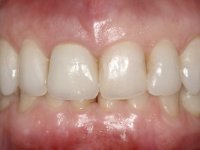

After the impression of the implant using a double-mix technique with double viscosity and the collection of shape and color information by the ceramist, we proceed with the work. In the model, a syn octa was placed over the implant, and a screw was placed on it to assess its emergence in relation to the incisal edge. Then, an adequate emergence profile in the artificial gingiva was prepared. A abutment with characteristics suitable for overbite and simultaneously capable of receiving a veneer was waxed on top of this scenario. This waxing gave rise to the manual milling of a very personalized abutment. An infrastructure in Zr was also made for the veneer with a very great adaptation to the abutment. On this infrastructure ceramics were placed. Ceramic fluorescence sought to compensate for the lack of fluorescence that Zr had and obviously further customize the aesthetics. The adhesive bridge was removed and the definitive work was placed. The syn octa was initially tightened with 35 N to the implant and then the Zr abutment was tightened over the syn octa with 15 N. The access hole was plugged and then the veneer was cemented with resin-reinforced glass ionomer. After 15 years, the patient returned to the consultation with tooth mobility. Fortunately, nowadays we have the possibility of having dynamic tightening wrenches that allow tightening screws with greater inclinations. An access cavity was made without damaging the incisal edge of the veneer. Tightening was done with a dynamic wrench with 15 N torque. The hole was covered with Teflon and filled with composite resin. This solution allowed the problem to be solved in a simple and economical way.